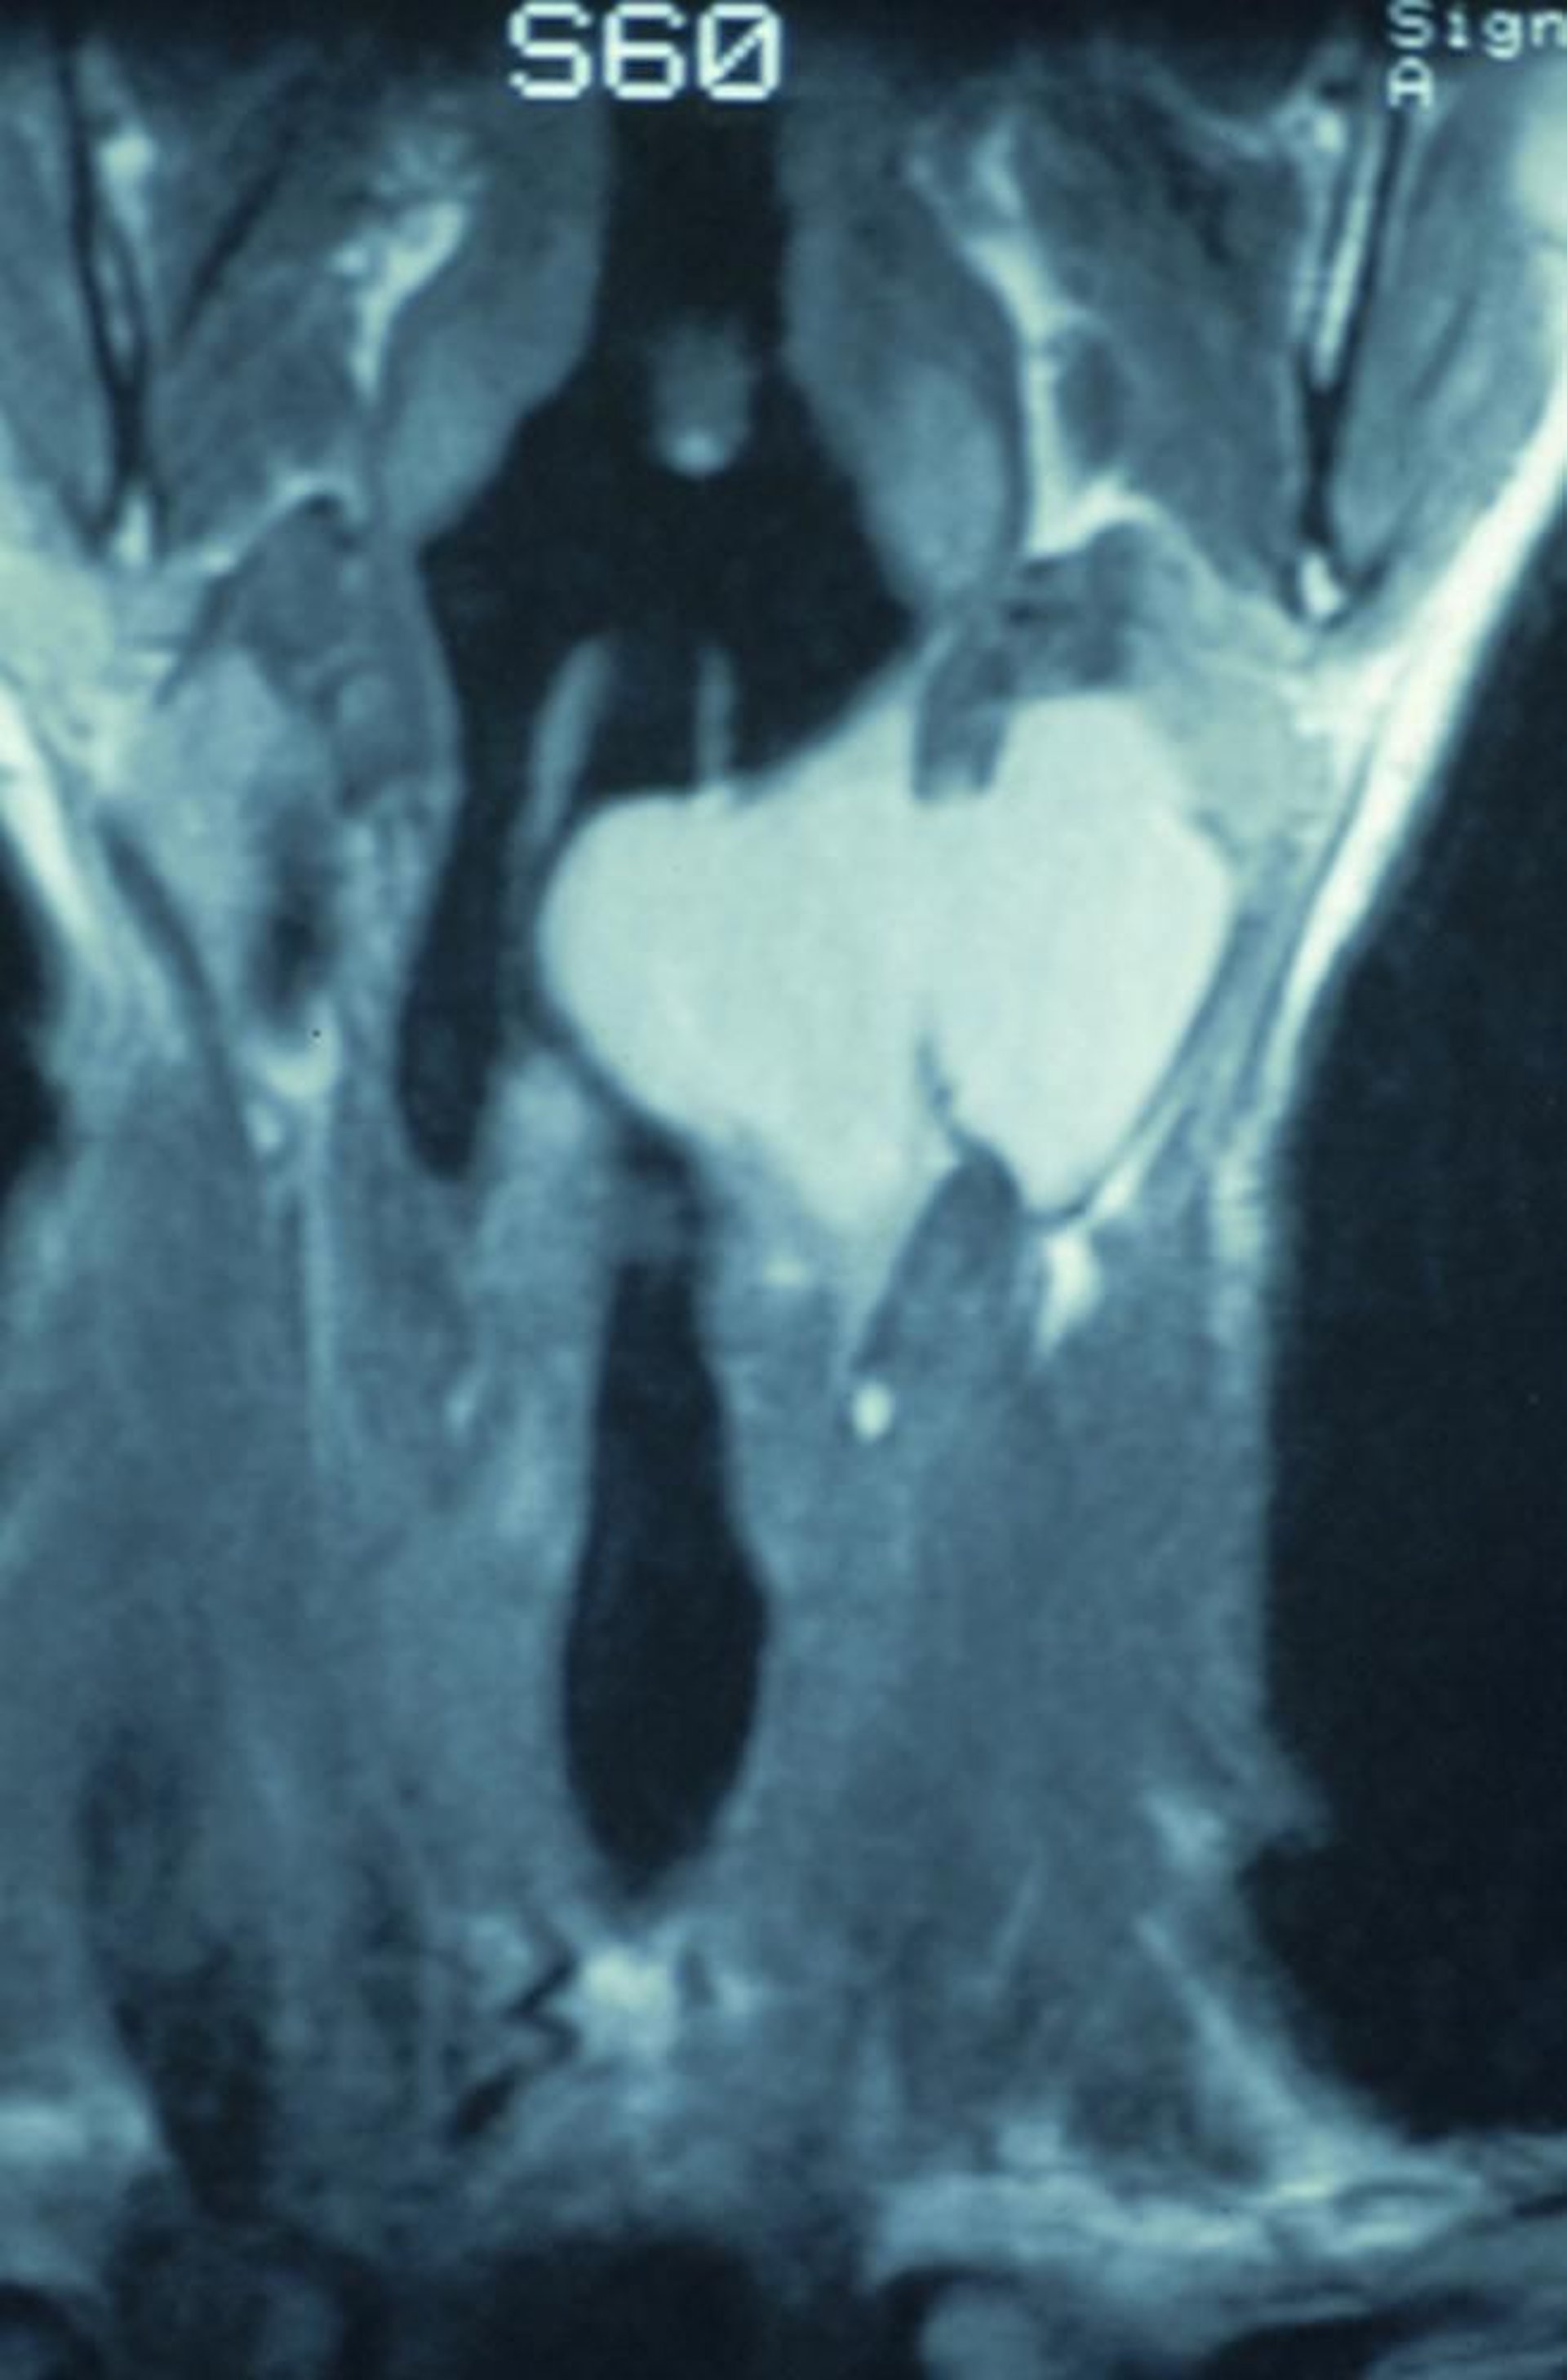

混合型の喉頭気嚢胞

このCT冠状断像は,喉頭内で発生して甲状舌骨膜を通って進展し,頸部に腫瘤を引き起こした混合型の喉頭気嚢胞を示している。

Image provided by Clarence T.Sasaki, MD.